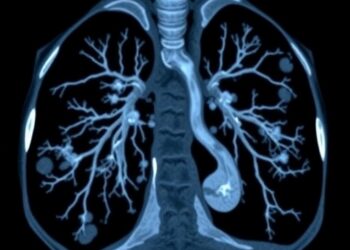

Lung Ultrasound Advances in Childhood Necrotizing Pneumonia

In the ever-evolving world of pediatric medicine, diagnostic technologies have continually reshaped the landscape of clinical care. One of the...